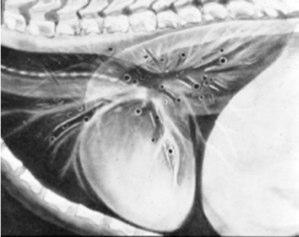

What is an air bronchogram?

Alveoli have accumulated fluid and therefore only air filled bronchi are visible